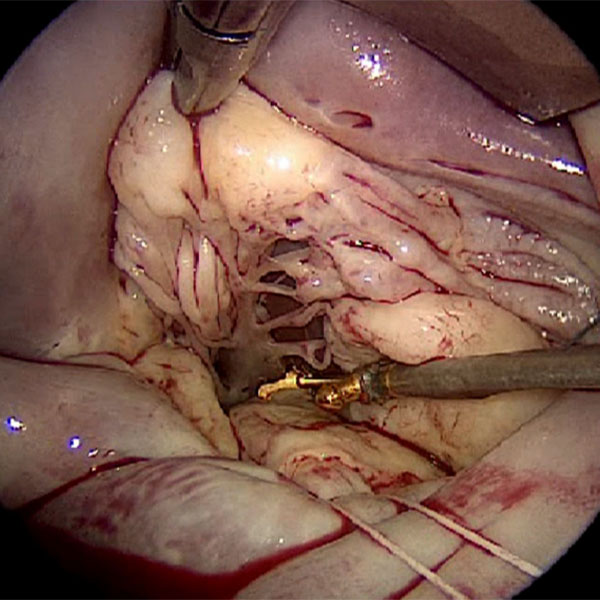

Minimally invasive mitral valve surgery is performed through a 4-5 cm incision in the patient's right chest without cutting open the sternum (breastbone). This technique can be used for: